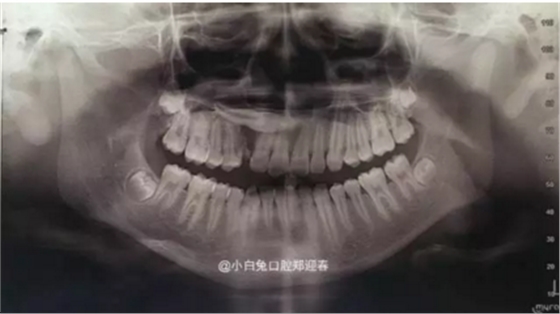

逆襲的阻生牙,牙醫(yī)該如何拯救你?

最近朋友圈轉(zhuǎn)發(fā)最多的一張片子,你知道嗎?

阻生齒外科聯(lián)合正畸治療

來(lái)源:小白兔口腔鄭穎春